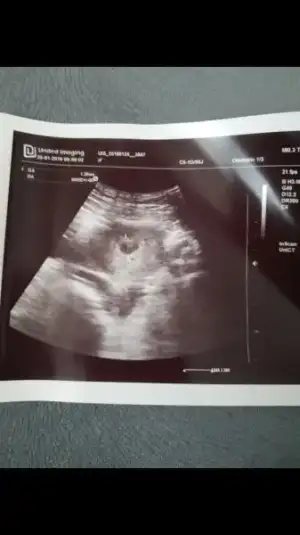

Biz bugün doktora gittik keseyi gördükk :)

Sata göre 5+6yız :KK200::anneadayı:

Doktor 6+2 gibi iyi dedi..

Haftaya da nasipse kalp atışlarını duyarız dedi.